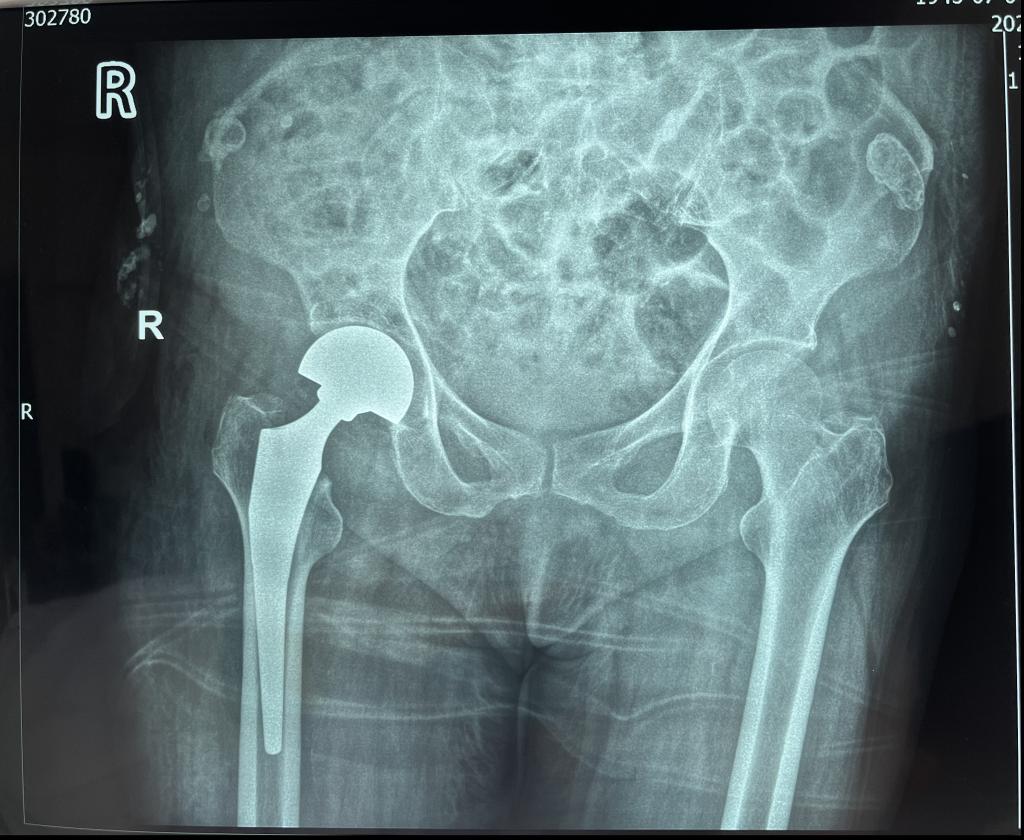

乐鱼手机站入口骨三科暨骨关节科是以关节疾病为主,涉及关节病、运动医学及关节周围骨折、老年脆性骨折为亚专业特征的学科。科室针对因骨质疏松引起的老年股骨颈骨折、股骨转子间骨折、胸腰椎体压缩性骨折等已成功开展数百例老年髋部骨折绿色急诊手术通道、微创人工股骨头置换术、微创股骨骨折内固定术以及经皮椎体成形术,并取得不菲成绩。